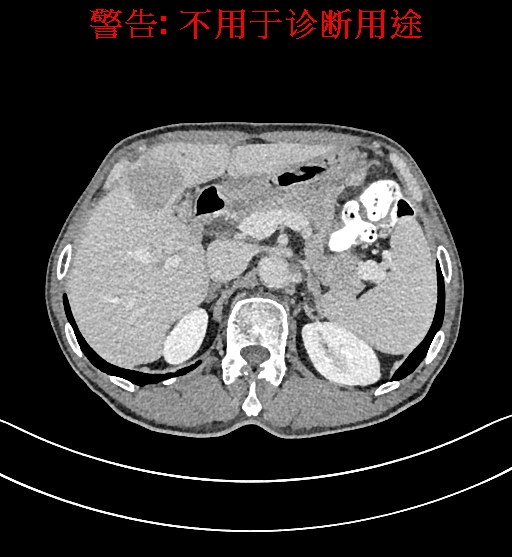

上腹部动态CT扫描示肝左内叶占位,考虑肝Ca可能性大,请结合临床肝多发小囊肿。

将0.625mm双源薄层CT资料的静脉期和动脉期Dicom格式文件导入海信CAS系统。

通过调节窗宽窗位调整CT序号,对肿瘤,肝实质,胆囊,下腔静脉,肿瘤,肝动脉、门静脉及肝静脉等进行三维重建;系统自动计算肿瘤体积和肝脏体积。模拟手术操作,自动计算切除肿瘤体积。肝脏体积为1320ml,肿瘤体积为37.88ml,通过比对70-80岁正常肝脏体积为1263.13±170.25 ml,通过术前模拟手术,精准判断切除后剩余肝脏体积能耐受,避免肝衰竭发生。

术前CT检查:

静脉期